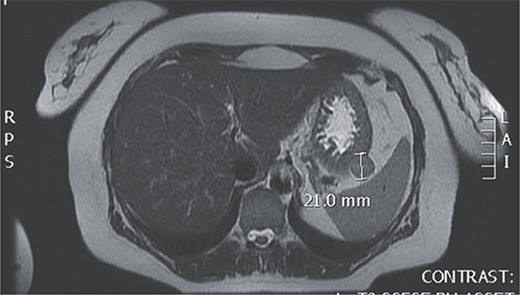

Upon admission to our hospital, the patient had malignant hypertension and a persistent headache that couldn’t be mitigated with the use of analgesics. Laboratory tests showed elevated serum levels of aldosterone under stress (472 ng/dL) (reference range: 1.3–23.3 ng/dL) and elevated levels of aldosterone at rest (64 ng/dL) (reference range: 1.4–15.6 ng/dL), with all the other laboratory findings including serum levels of minerals, Hromangin A, urine levels of methanephrin in the reference range. An MRI finding showed a GIST tumor at the posterior of the fundus of the stomach (Fig. 1).

Magnetic resonance of GIST at the posterior of the fundus of the stomach.